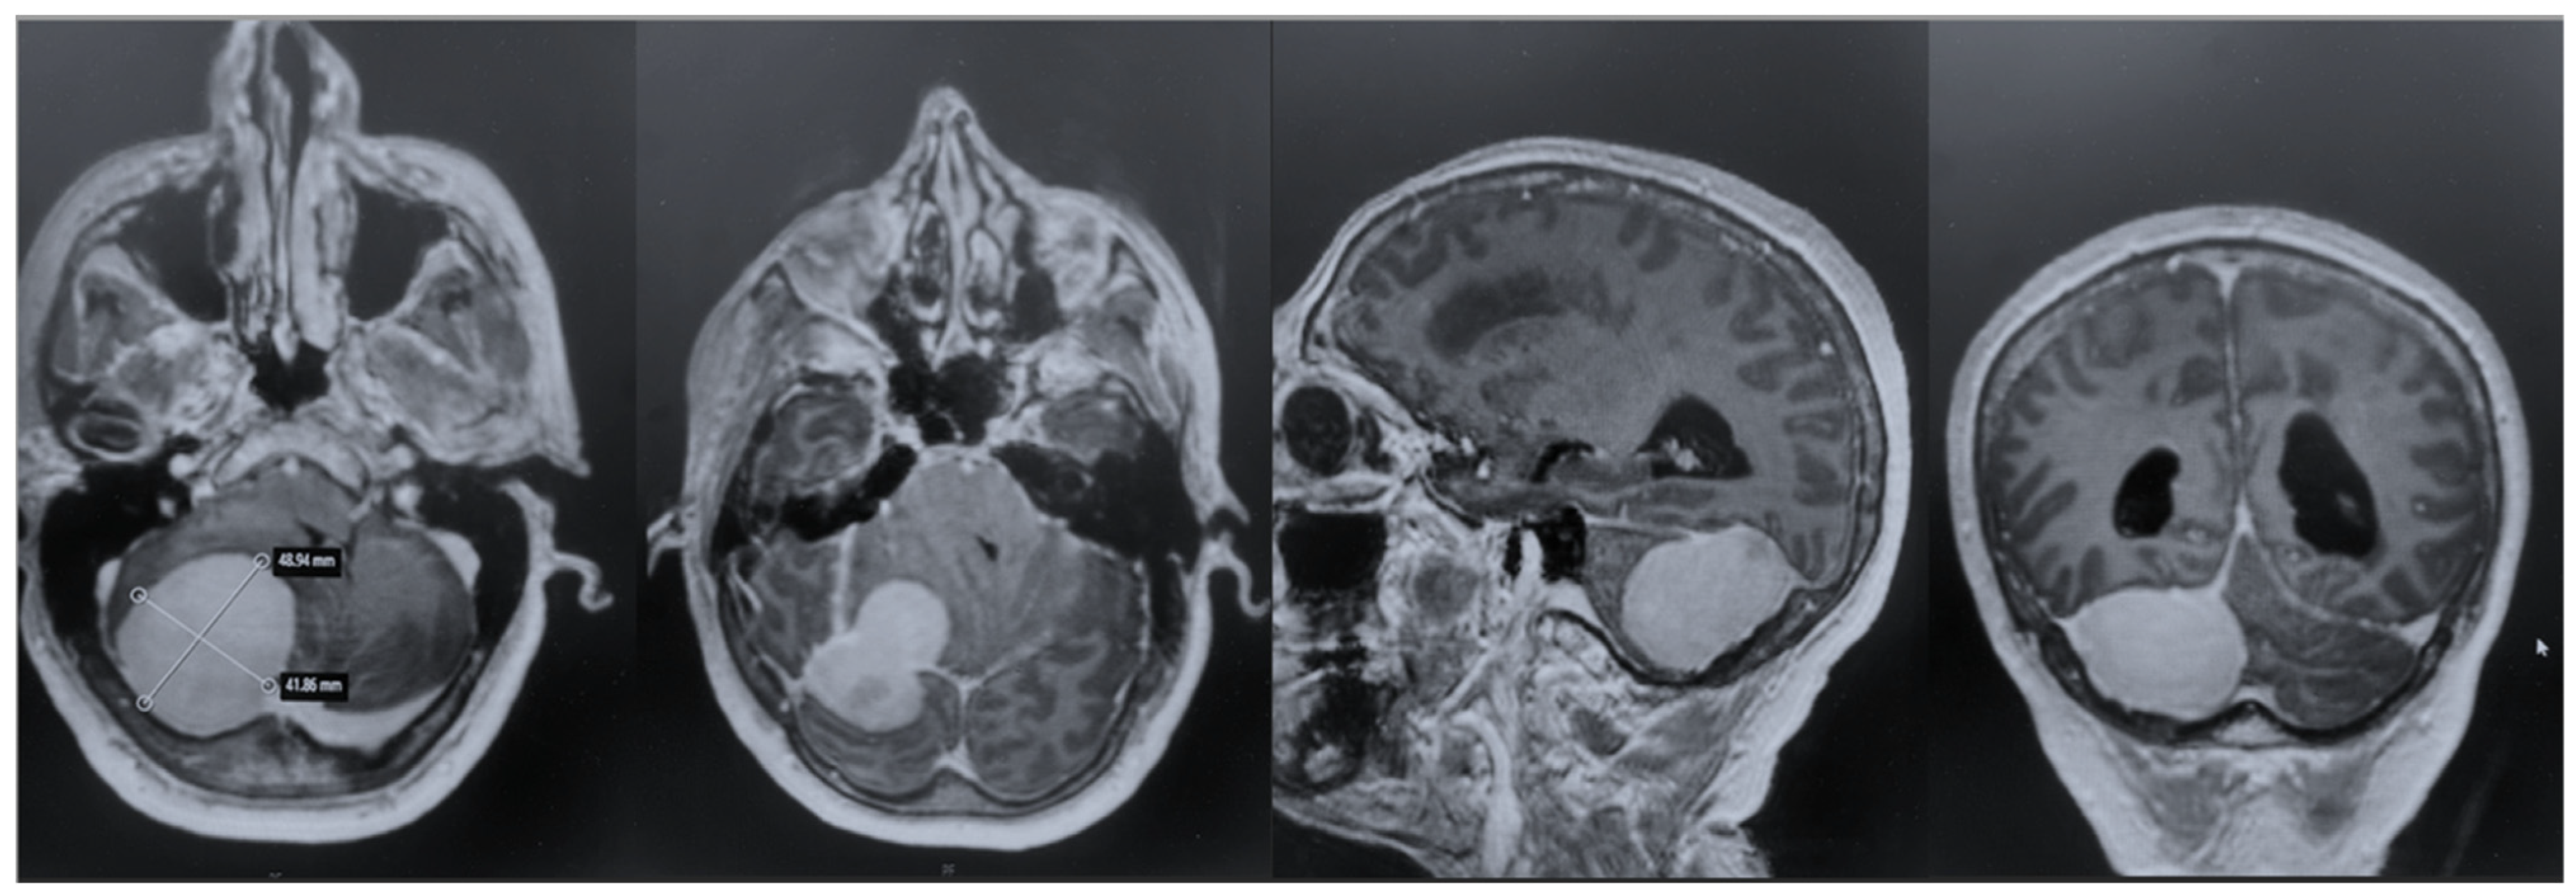

The patient underwent an early postoperative MRI, which documented the complete resection of the lesion without any postoperative complications (Figure 4). The patient was discharged with a significant improvement in the neurological examination at 7 days after surgery. Histopathology confirmed a diagnosis of meningioma, WHO grade 1, subtype fibrous.

Figure 4. Postoperative MRI + c: these pictures show the gross total resection of the lesion with no signs of postoperative complications.